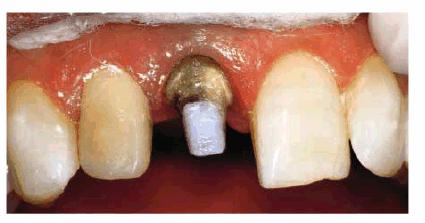

concept is supported by most studies. Such a patient can be seen in Figur 323s1823d es 18-10A 18-10B to G, and 18-10H. Post restorations used in anterior

Figur 323s1823d e 18-10A: This young lady fractured her left central and lateral incisors in an accident. Because the original teeth had protruded before fracturing, the patient requested that the restoration be accomplished with an improved appearance in the most permanent treatment available.

Figur 323s1823d e 18-10B to G: Following endodontic therapy, two cast posts were constructed and cemented to place in the prepared incisors.

Figur 323s1823d e 18-10H: The final all-ceramic crowns were bonded to place. Note the natural result of both the shade and texture of the crowned teeth.